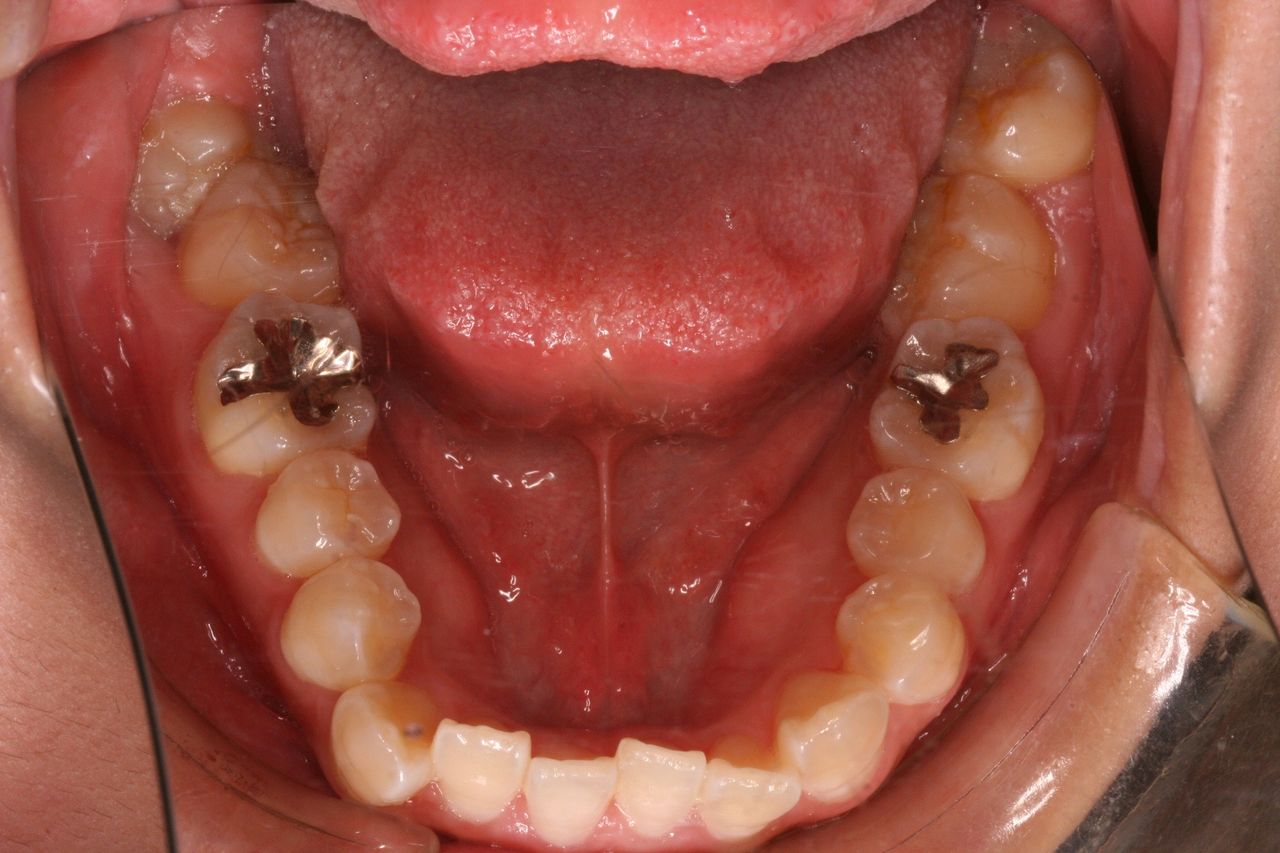

上方向からみると奥歯が頬方向に傾いております。

つまり例としては1と3に当てはまります。

上の奥歯の部分を注目してください。親知らずの前の歯が2本抜歯してるのがわかると思います。

つまり、この時点で上顎だけで3本も抜歯してます。そういう意味では患者さんは不安になりますかね(笑)